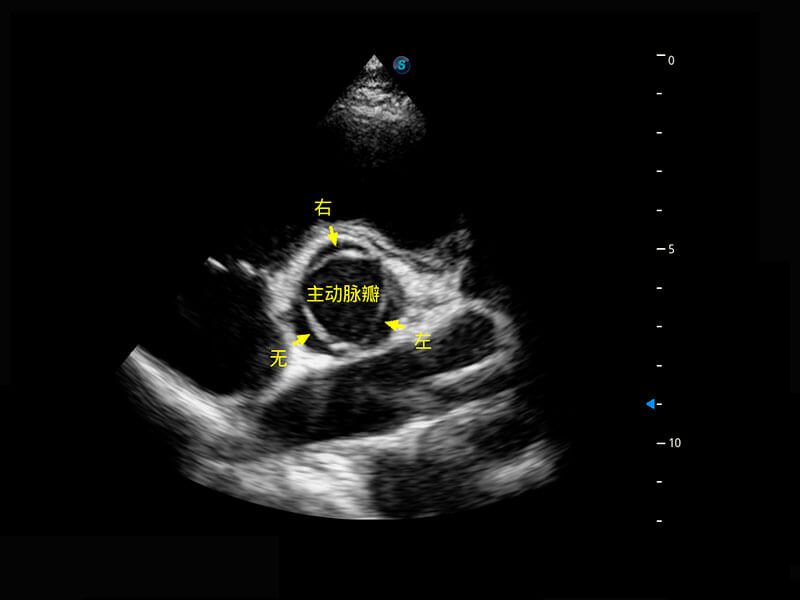

P60搭載一系列胎兒心臟成像技術(shù),實(shí)現(xiàn)精細(xì)的胎兒心臟評(píng)估。

右室雙出口